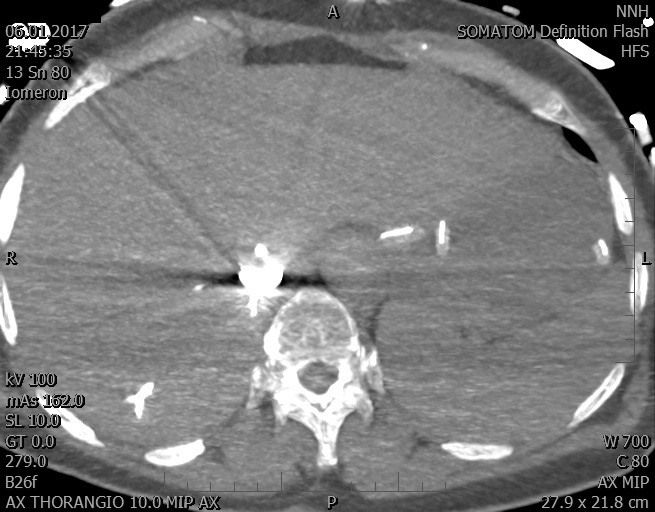

Video 2 - Echokardiograficky byla zjištěna těžká dysfunkce dilatační levé komory s nezvětšenou pravou komorou.Pro nejasnou příčinu zástavy jsme provedli i vyšetření výpočetní tomografií (CT), které vyloučilo plicní embolizaci (série 1 - soubory na konci článku). V den přijetí při přetrvávající oběhové nestabilitě byla nemocná opakovaně defibrilována pro fibrilaci komor se stabilizací rytmu po podání amiodaronu a mesocainu. Dle hemodynamických měření se jednalo o těžký kombinovaný šok. Vstupní laboratorní vyšetření bylo bez větších pozoruhodností. Posléze jsme doplnili anamnézu od příbuzných a zjistili, že pacientka užila do dvou hodin před srdeční zástavou první tabletu amoxicilinu na lehký respirační infekt. Při nevýtěžnosti vstupních vyšetření a nových anamnestických informacích jsme doplnili 14 hodin po kolapsu vyšetření koncentrace tryptázy v séru, která byla extrémně zvýšena (tabulka 2), což nás vedlo k podezření na anafylaxi.